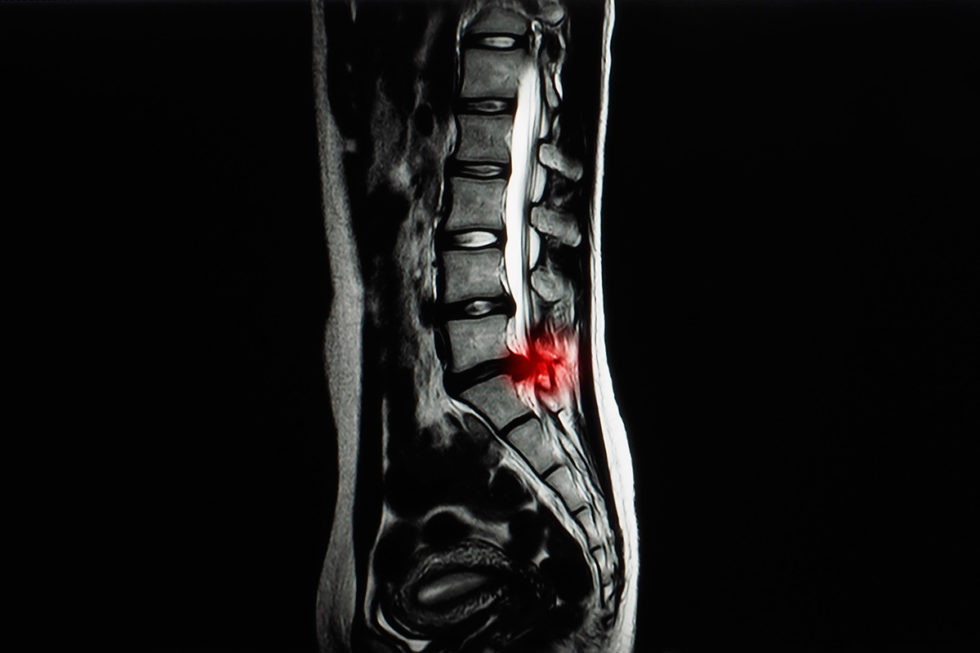

Hernia Lumbar Y Cervical . El dolor y los signos relacionados con la hernia discal cervical suelen sentirse en un brazo o en el otro. En este artículo voy a explicarte cuáles son los síntomas graves de hernia discal para que puedas identificarlos y buscar ayuda de inmediato. Con un disco herniado en la región lumbar, usted puede tener dolor punzante en una parte de la pierna, la cadera o los glúteos, y entumecimiento en otras partes. La hernia se produce como consecuencia de la salida del contenido del interior de un disco de la zona baja de la. Se caracteriza por tener episodios de dolor en el cuello debido a algún tipo de esfuerzo o de mantenimiento de una postura viciada. En cada nuevo episodio, el dolor tarda más días en. Los síntomas pueden variar en función del disco que se haya herniado y de la raíz nerviosa que se haya pinzado o inflamado. This, in turn, will cause symptoms at c6 and c7, respectively. En la mayoría de los casos de hernia de disco, un examen físico y los antecedentes médicos son todo lo que se.